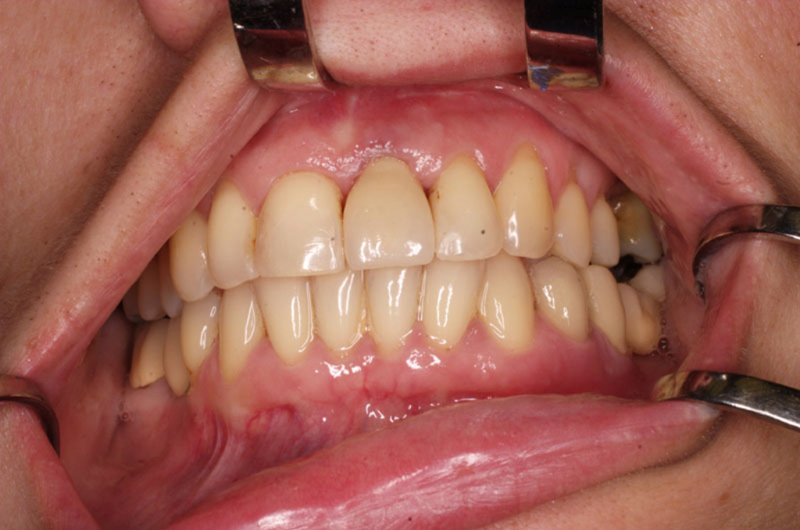

Náhrada jednoho zubu pomocí implantátu je možná také v postranním úseku chrupu. Při ztrátě většího počtu zubů ve frontálním nebo postranním úseku může být mezer uzavřena větším počtem jednotlivých implantátů.

Při ošetření pomocí jednotlivých implantátů zůstávají sousední zuby neporušené – intaktní. Při klasickém ošetření pomocí můstků musejí být tyto zuby obroušeny!